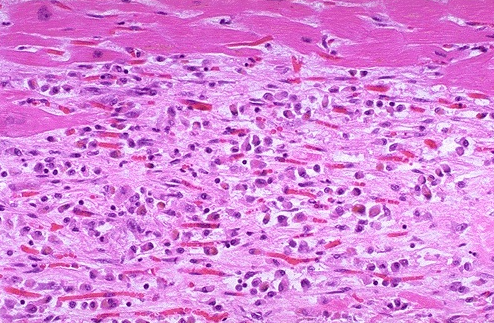

8

Q

What do you see?

A

- At 3 to 4 weeks of age the intermediate myocardial infarction shown involving a papillary muscle at low power above and medium power below have decreasing cellularity along with more prominence of collagen

- Note the remaining normal red myocardial fibers. Cardiac biomarkers are not positive at this stage and myocardial rupture is unlikely. The degree of cardiac failure depends upon the extent of myocardial loss